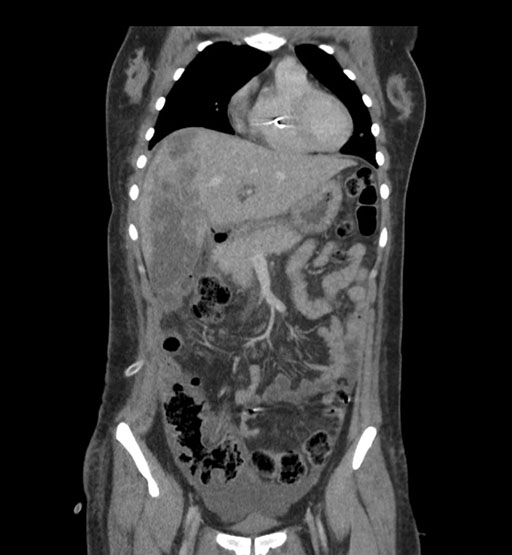

Imaging Analysis

Look through the patient's CT scan to identify any areas of concern for the necessary procedure.

Coronal Venous